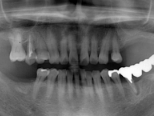

全身状態の問診と口腔内の診査を行った後、あごの骨の量と質を記録するため、お口の中の型を取るのと同時にレントゲン・CT撮影を行います。当院では、CT撮影後、コンピューター上でソフトを使用し、診査・診断を行います。これらのデータを用いて、一人ひとりの患者様に合った最適な治療計画をご提案します。

症例写真(レントゲン)